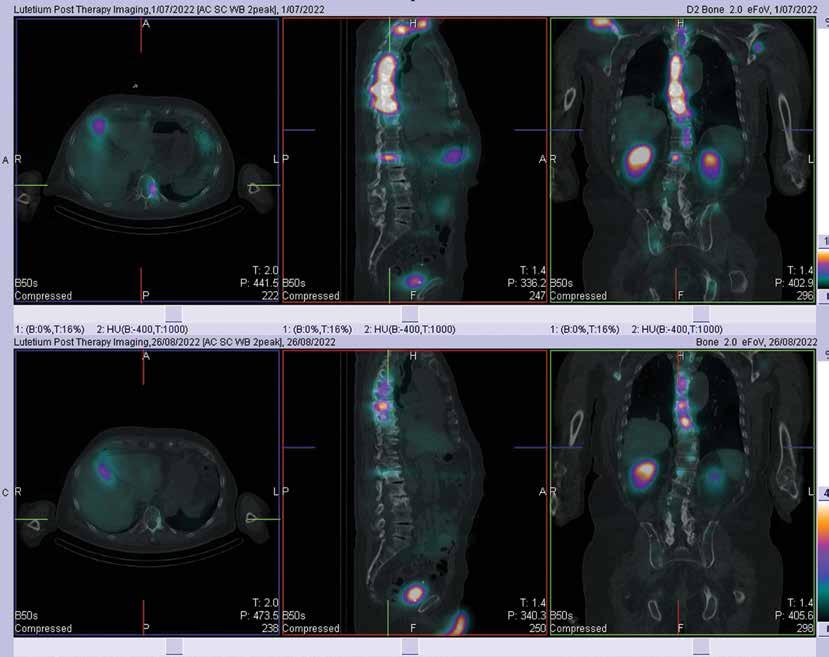

Oakley L, Soh S-E, Kimmel L, Mulvey N, Curtis H, Holland AE. (2022) The impact of obesity in rehabilitation: a mismatch between staff perception and hospital outcomes. Disabil Rehabil 44(3):363-9.

O’Connor DA. Cochrane Podcast - Arthroscopic surgery for degenerative knee disease, interview by Ray Moynihan, 30 June 2022.

O’Connor D, Johnston RV, Brignardello-Petersen R, Poolman RW, Cyril S, Vandvik PO, Buchbinder R. (2022) Arthroscopic surgery for degenerative knee disease (osteoarthritis including degenerative meniscal tears). Cochrane Database Syst Rev 3:CD014328.

O’Keeffe M, Michaleff ZA, Harris IA, Buchbinder R, Ferreira GE, Zadro JR, Traeger AC, Thomas R, Belton J, Darlow B, Maher CG. (2022) Effect of diagnostic labelling on management intentions for non-specific low back pain: A randomized scenario-based experiment. Eur J Pain 26:1532-45.

Oliveira C, Hamilton M, Traeger A, Buchbinder R, Richards B, Rogan E, Maher CG, Machado GC. (2022) Do Patients with Acute Low Back Pain in Emergency Departments Have More Severe Symptoms than Those in General Practice? A Systematic Review with Meta-Analysis. Pain Med 23(4):614-24.

Pajari J, Jokihaara J, Waris E, Taimela S, Järvinen T, Buchbinder R, Karjalainen T. (2022) Responsiveness of different pain measures and recall periods in people undergoing surgery after a period of splinting for basal thumb joint osteoarthritis. BMC Med Res Methodol. 22(1):37.

111 110 CABRINI RESEARCH | Annual Report 2021-22 CABRINI RESEARCH | Annual Report 2021-22

PUBLICATIONS PUBLICATIONS

Ponkilainen V, Karjalainen TV, KuitunenI, Uimonen M, Johnston RV, Saarinen A, Whittle SL, Avery JC, Glennon V, Grobler L, Buchbinder R. (2022) Perioperative use of disease modifying anti-rheumatic drugs DMARDs) in people with inflammatory arthritis (Protocol). Cochrane Database Syst Rev 5:CD015096.